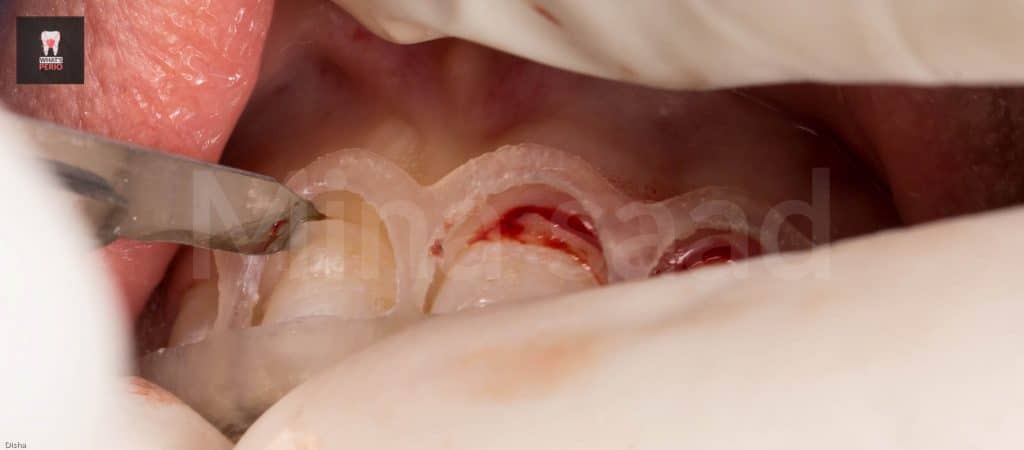

-External bevel gingivectomy was made while the guide in place.

-Internal bevel incision was made “envelope flap” to expose underlying labial plate of bone.

-Care was taken during flap elevation to make a split-thickness incision under each papilla to preserve underlying periosteum interdentally as there is no need to expose interdental bone.

-The guide was placed again over labial plate of bone & it was noted that its apical level is higher than alveolar crest level.” Which confirms that the design on CBCT was accurate”